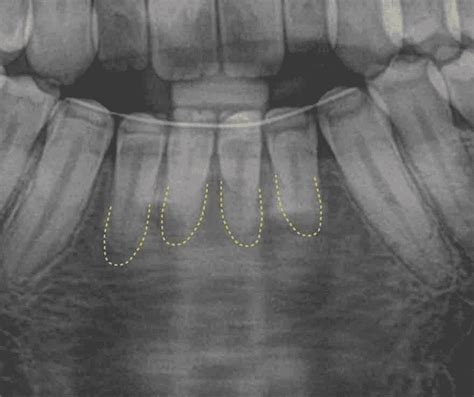

Reabsorción Radicular: Un Aspecto Importante

La reabsorción radicular es la pérdida de tejido dental como resultado de la acción odontoclástica. Puede ser interna o externa y su etiología es compleja y multifactorial, incluyendo la variabilidad biológica individual, la predisposición genética y factores mecánicos como el tipo de aparatología, la técnica utilizada, el movimiento realizado, la dirección y magnitud de las fuerzas aplicadas, la duración del tratamiento y la severidad de la maloclusión.

La reabsorción radicular apical externa (RRAE) se describe como un proceso fisiológico o patológico con pérdida de cemento o dentina, dando como resultado un acortamiento del ápice de la raíz. Las reabsorciones se clasifican en externas e internas.

La etiología de la reabsorción radicular tiene dos fases: un estímulo y una reestimulación. El estímulo afecta los tejidos no mineralizados, como el precemento o el tejido cementoide, que cubre la superficie externa de la raíz. Este estímulo puede ser de tipo mecánico o químico. El tejido mineralizado expuesto es colonizado por células multinucleadas, las cuales inician el proceso de reabsorción. Si no hay una estimulación continua, el proceso finalizará espontáneamente y se producirá la reparación con cemento nuevo a las dos o tres semanas.

La reabsorción se ha documentado en un 19-31,4% de los pacientes sometidos a tratamiento de ortodoncia, siendo mayor su prevalencia en los incisivos superiores e inferiores. La magnitud de la fuerza ortodóncica ha demostrado ser un factor principal en la reabsorción radicular. La mayoría de los estudios indican que existe una correlación positiva entre la cantidad de fuerza aplicada y la severidad de la reabsorción.